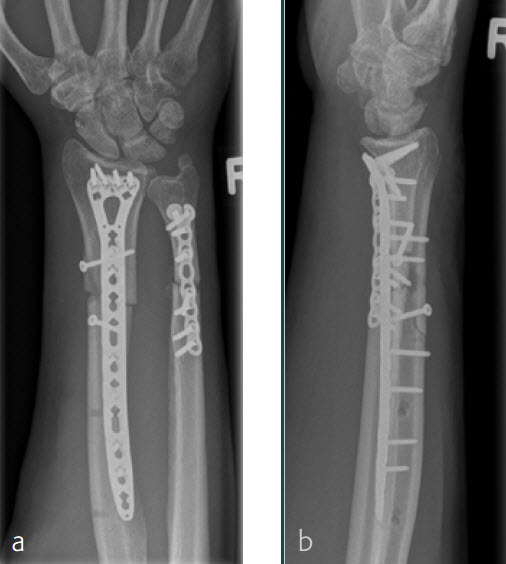

A 26-year-old man suffered a multifragmentary fracture of his left distal radius with extension into the diaphysis (AO23 C3.3) (Fig 2). The VA LCP Extra Long Two-Column plate was used for fixation (Fig 3). After initial immobilization, the plate provided a good postoperative fixation of the fracture.

The fracture showed primary bone healing without callus formation. At the 3-month follow-up, the patient was full weight bearing with excellent clinical function (Fig 4). The radiological follow-up can be technically challenging due to the correct focus of the central ray.